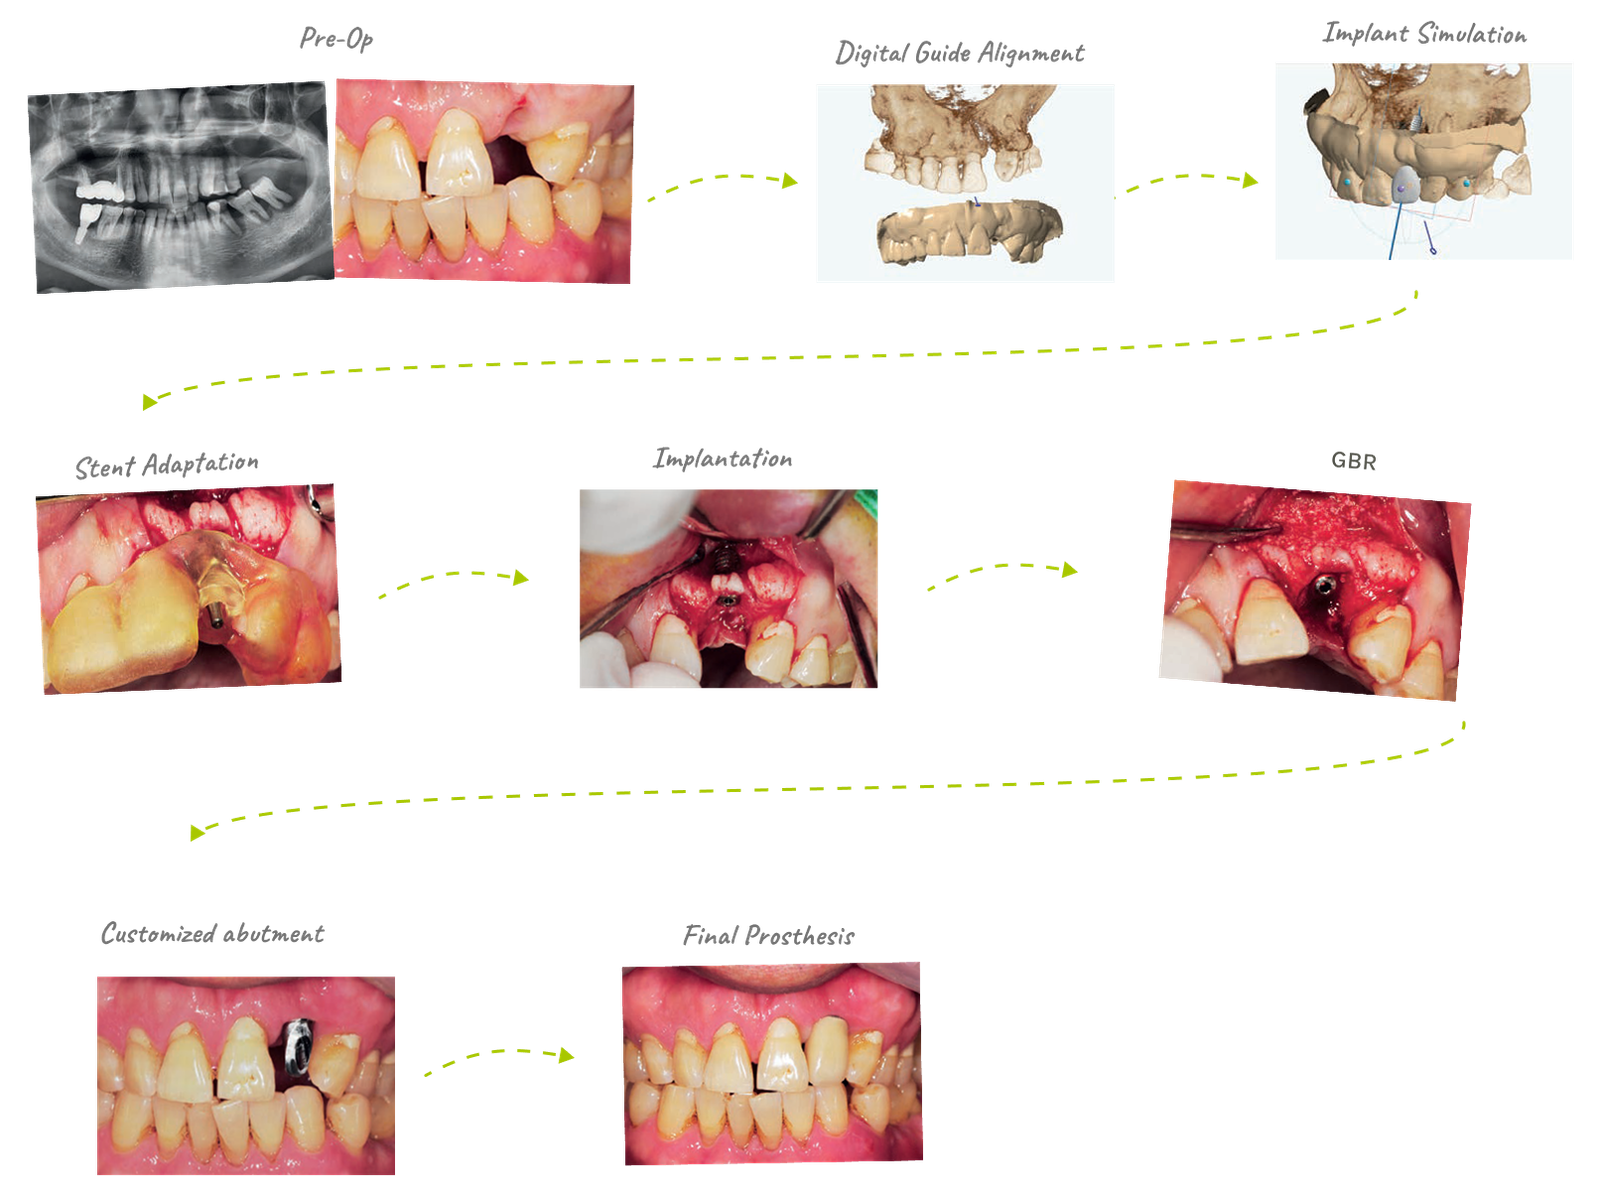

57yrs / Male | Implant Parts #22 | Fix Size: SuperLine 4008 | Guide Kit: Full Kitt

The overall process is similar to the existing guide program, and since it is in the early stages of production, detailed performance improvement is necessary for possible parts. However, there is no major difficulty in undulating implant placement, and as it is a guide program produced with domestic technology, it quickly reflects the needs of clinicians, making it a promising program for the future.

It takes at least one week to produce through a request from the center, but if you design your own using Dentium Digital Guide Software, you can produce it within 30 minutes to an hour. When weeding the guide, pay attention to the ct alignment, and when making the guide, the undercut and border should be well set to fit the patient's mouth. It is recommended to use the anchor pin function for stability.